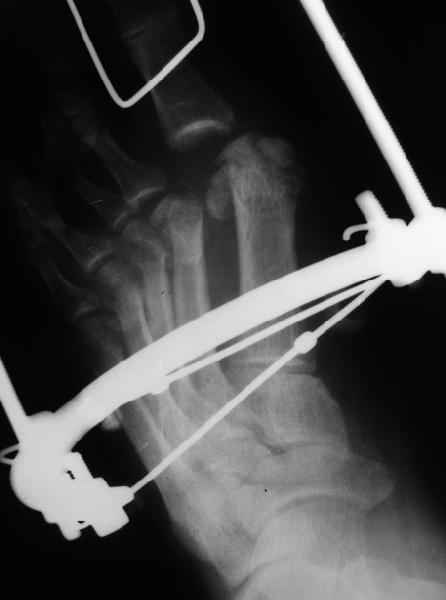

1 передний отдел стопы делается в косой, а не боковой проекции - на боковой все плюсневые кости накладываются друг на друга, и ничего не видно - это же аксиоматично! Я, например, на прямых проекциях не вижу совсем признаков перелома первой и четвертой плюсневой, и сомневаюсь в переломе третьей, боковые же совершенно неинформативны.

Они же наложили дистракционный аппарат (вместо того, чтоб сделать открытое вправление зафиксировать это одной спицой Киршнера), продержали больного две недели в аппарате (ЗАЧЕМ?), а теперь спрашивают , что делать...

Вы говорите "Да, снимки не лучшие, но суть проблемы на них видна ведь."

Как же суть проблемы видна? Человек говорит о переломе первой (то есть речь идет о переломо-вывихе?), второй, третьей и четвертой плюсневых костей, а я вижу только перелом второй. мне кажется, что проблема в таком случае будет чуть-чуть другая. Кстати, сколько переломов насчитали на этих снимках Вы?

Имеем - без малого двухмесячные переломовывихи перeднего отдела стопы , больной в отделении 20 дней, доктор думает, что ему делать:

1 полное смещение второй плюсневой, которое НАВЕРНЯКА приведет к появлению натоптыша и невозможности нагружать передний отдел стопы - всеми участниками просто игнорируется.

Не знаю, что за проблема, но я на своем мониторе переломы отлично вижу.

Та же проблема - по крайней мере на снимке в аппарате (фас) отчетливо видно перелом ее головки.